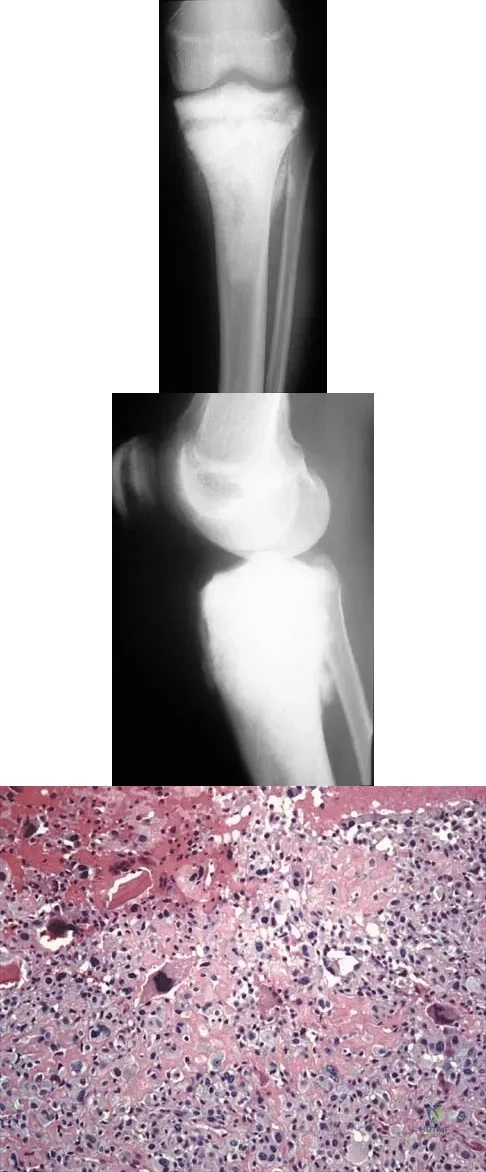

A 15-year-old girl reports a 6-month history of activity-related knee pain and swelling. A radiograph, MRI scan, and biopsy specimen are shown in Figures 21a through 21c. What is the most likely diagnosis?

Explanation

A 15-year-old girl has left knee pain and an enlarging mass in the distal thigh. AP and lateral radiographs are shown in Figures 52a and 52b, and a biopsy specimen is shown in Figure 52c. What is the most likely diagnosis?

Explanation

Figures 19a and 19b show the AP and lateral radiographs of an 18-year-old man who has had knee pain for 3 months. Figure 19c shows a histopathologic photomicrograph of the biopsy specimen. Which of the following factors is most likely to affect his survival?

Explanation